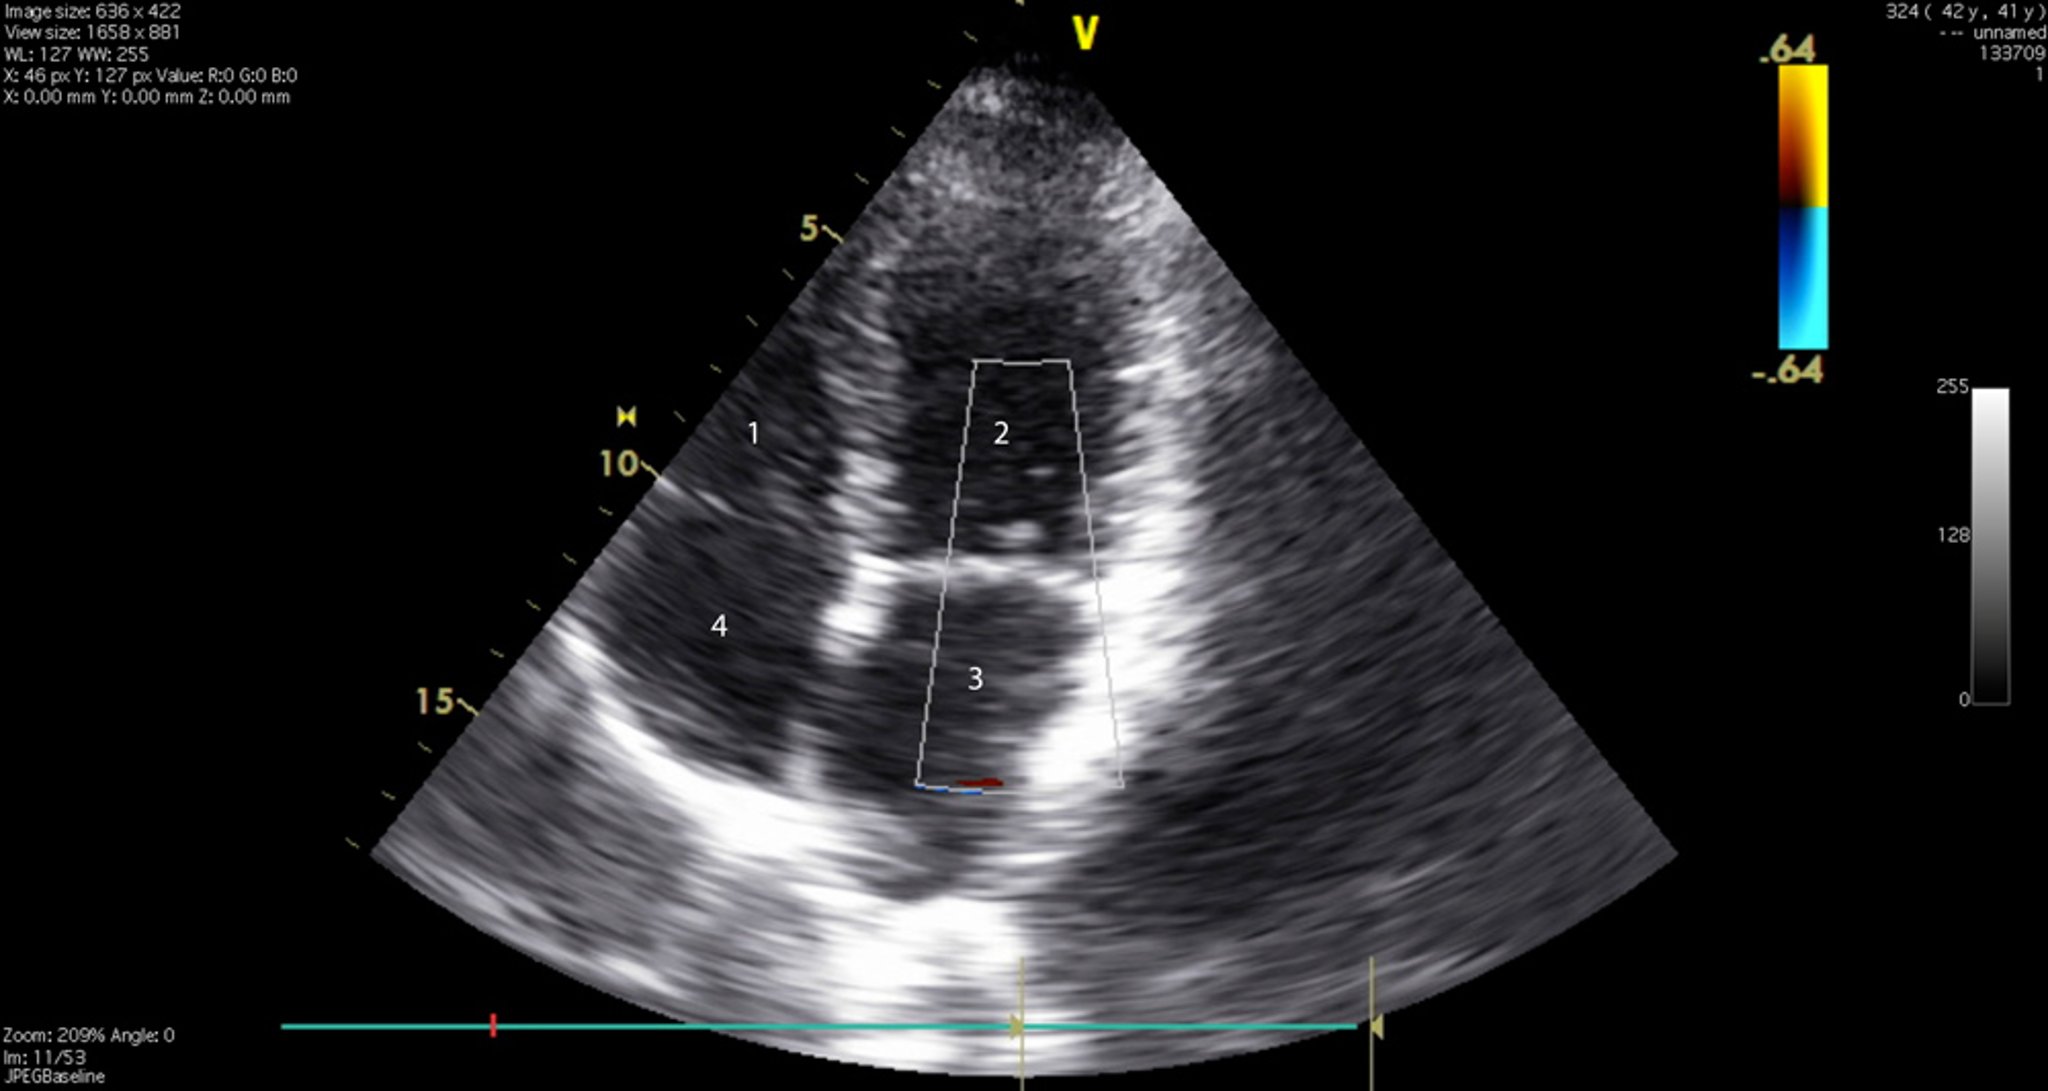

Essa imagem mostra as 4 câmaras cardíacas e as valvas tricúspide e mitral. 1 = ventrículo direito; 2 = ventrículo esquerdo; 3 = átrio esquerdo; 4 = átrio direito.